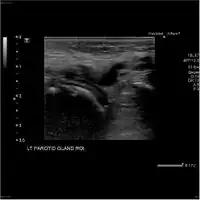

-

Acute left parotid sialadenitis -

Acute left parotid sialadenitis